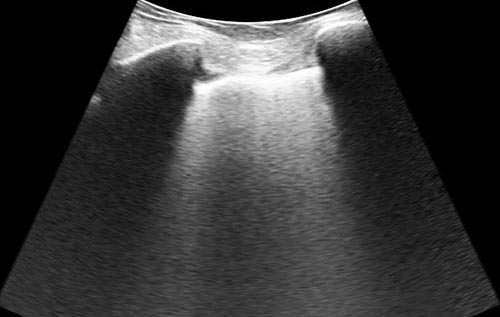

Semana 5

Paciente dá entrada no DE com insuficiência respiratória, com necessidade de intubação orotraqueal. Realizado ultrassom beira leito logo após o procedimento, com a seguinte aquisição de imagem. Que estrutura podemos ver?